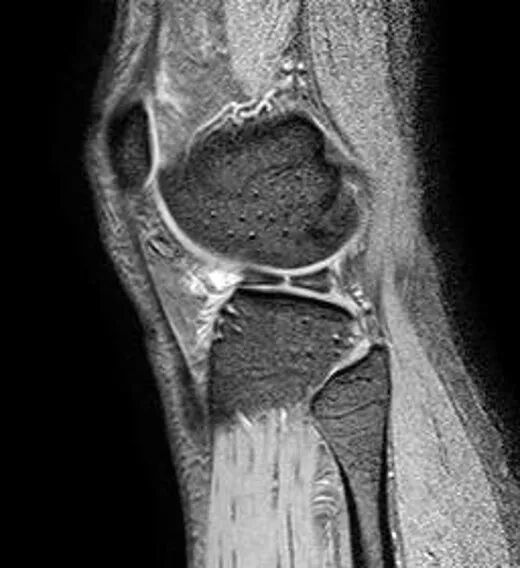

半月板撕裂定义与显示

1、半月板显示:以T2-WI加脂肪抑制为最好.2、半月板病变:最常见损伤是撕裂伤3、病因:慢性退变性撕裂和急性外伤性撕裂4、诊断方法:当半月板内出现线样高信号到达其游离缘或关节面时,即可诊断半月板撕裂5、病变信号变化:T1WI为线样稍高信号,T2(FS)或T2*WI信号更高6、半月板球形及线行高信号影未达关节面,为其慢性损伤或退行性改变(变性)7、MR诊断半月板撕裂的准确度达90-97%,特异性为94%,假阳性高于假阴性,主要是将膝横韧带与外侧半月板相邻的国肌腱鞘等误认为半月板撕裂.

最常见类型:斜行撕裂表现为:在矢状面上见III级高信号到达半月板关节面的上缘或下缘

半月板斜行撕裂